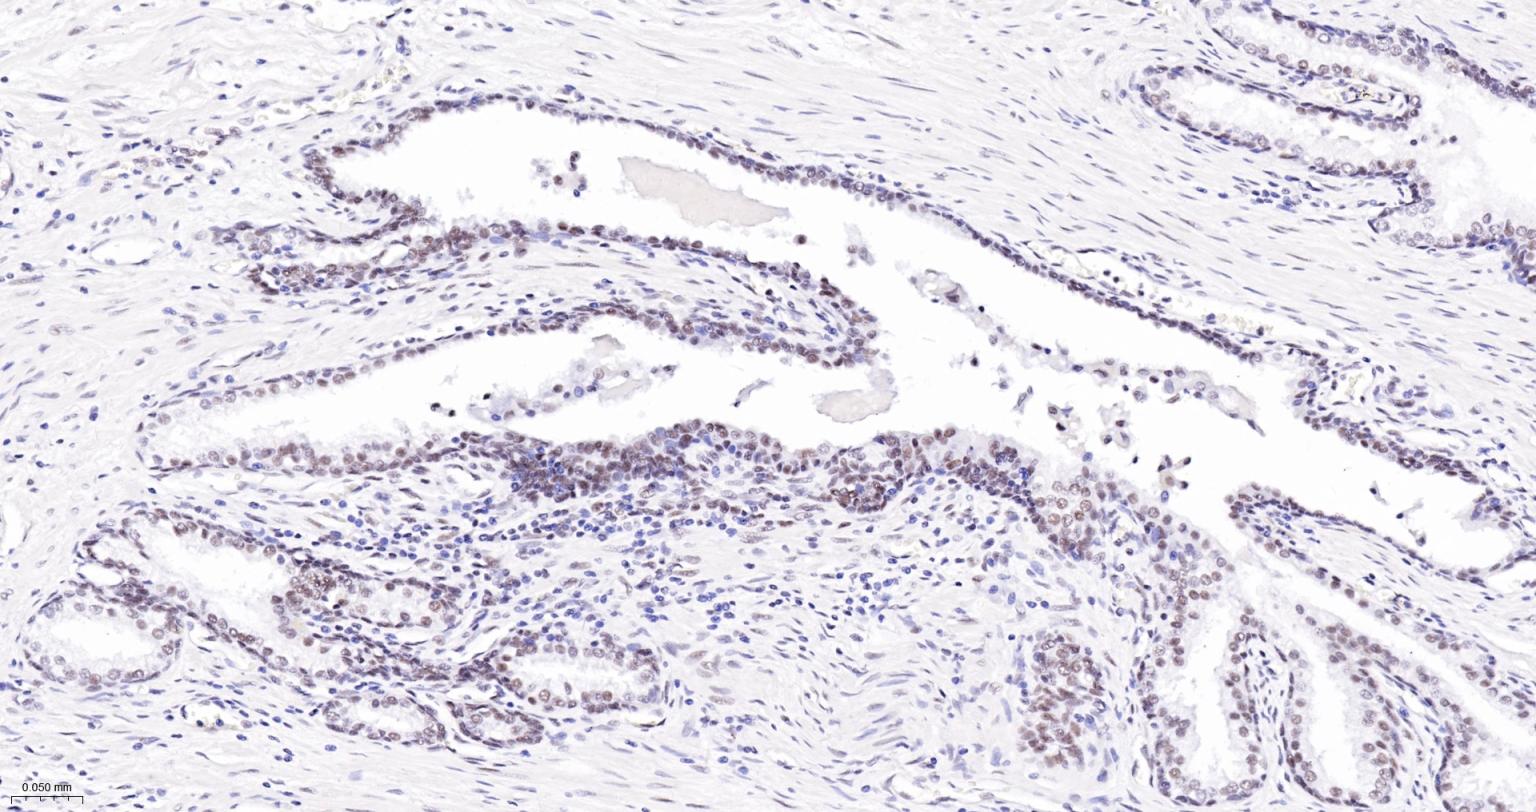

Paraformaldehyde-fixed, paraffin embedded Human Endometrial Cancer; Antigen retrieval by boiling in sodium citrate buffer (pH6.0) for 15 min; The section was incubated with USP39 Monoclonal Antibody, Unconjugated (bsm-63016R) at 1:200 overnight at 4°C, followed by conjugation to the bs-0295G-HRP and DAB (C-0010) staining.